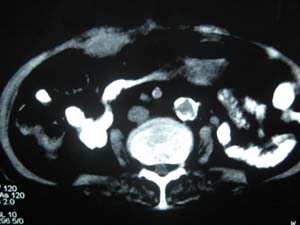

标题: CT15625:女性78Y,十天前胃镜示胃穿孔,现低热 [打印本页]

标题: CT15625:女性78Y,十天前胃镜示胃穿孔,现低热

肝脓肿/膈下脓肿?

膈下脓肿

隔下肿脓.

支持--膈下脓肿

膈下及肝脓肿。

考虑多发性肝脓肿。